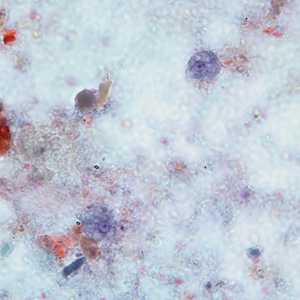

E. coli trophozoites stained with trichrome.

Figure A: Trophozoite of E. coli stained with trichrome.

Figure B: Trophozoite of E. coli stained with trichrome.

Figure C: Trophozoites of E. coli stained with trichrome.

Figure D: Trophozoite of E. coli stained with trichrome.